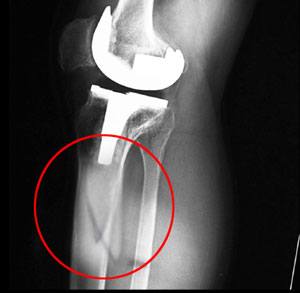

Knee replacement, also called knee arthroplasty, is a surgical procedure in which the worn-out or damaged surfaces of the knee joint are removed and replaced with artificial implants. Any resulting fractures or breaks in the bone around the implant are called periprosthetic knee fractures. These fractures may occur during surgery (intraoperative) or after surgery (postoperative), and usually involve the patella, tibia or the femur (kneecap, shinbone, and thighbone). Women are at higher risk than men.

Joint-Revision Surgery: Some cases of periprosthetic knee fracture are caused by a loose implant. Joint-revision involves the removal of the old implant and placement of a new implant with special components to treat the fracture.

Open Reduction and Internal Fixation (ORIF): Some cases of periprosthetic knee fractures do not require replacement of the implant and the fractured bone fragments are fixed together with the help of screws.